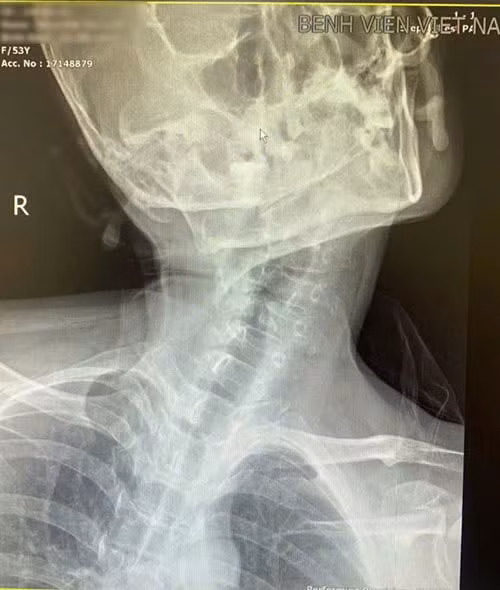

Tình trạng vẹo cột sống cổ của người bệnh - Ảnh BVCC

dat-noi-khi-quan1.jpg